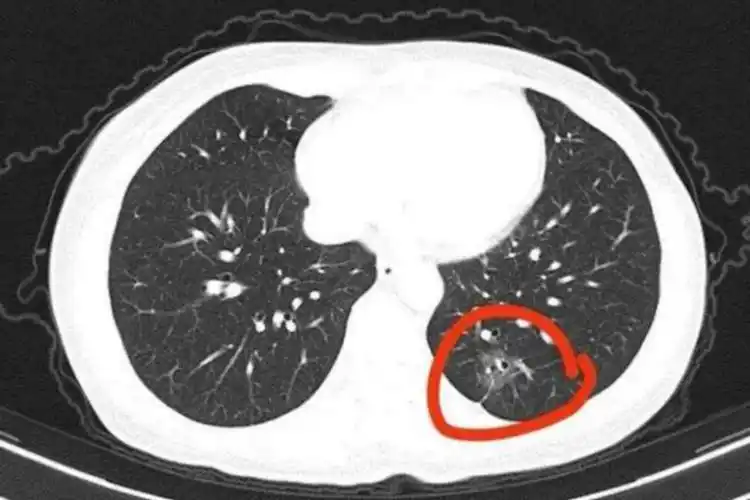

早期肺癌ct图

这个肺部肿瘤藏得深,胸片分分钟漏诊,追踪下来该来的都来了 [病例帖]

世界肺癌日:一起关注如何发现早期肺癌